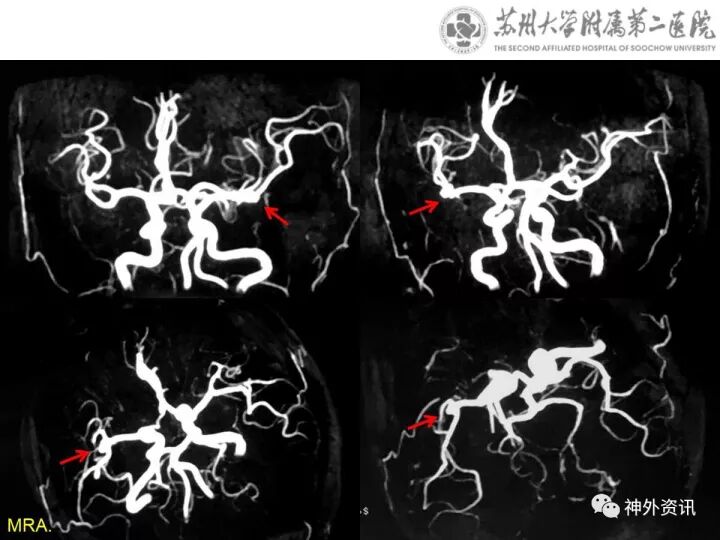

颅内多发动脉瘤右翼点锁孔入路夹闭术